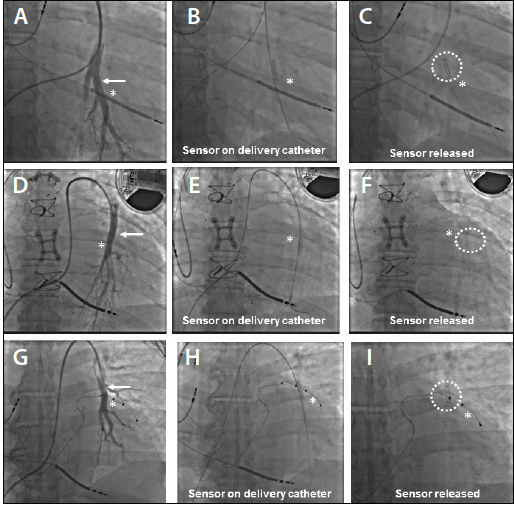

Figure 3. Fluoroscopic markers are used to identify the planned implant location. Implant site (arrow) with asterisk indicating that the implant site is superior to the rib (A). Sensor on the delivery catheter prior to release (asterisk) (B). Sensor (dotted circle) released to the desired location (asterisk) (C). Implant site (arrow) with asterisk indicating that the site is adjacent to the rib (D). Sensor on the delivery catheter prior to release (asterisk) (E). Sensor (dotted circle) released to the desired location (asterisk) (F). Implant site (arrow) and asterisk indicating that the implant site is adjacent to the left ventricular lead (G). Sensor on the delivery catheter prior to release (asterisk) (H). Sensor (dotted circle) released to the desired location (asterisk) (I).

The ideal location for the implant is a left-sided, posteriorly directed PA branch measuring 7 to 11 mm in diameter with an appropriate distal vessel length to allow a stable and safe position for the 0.018-inch guidewire (Figure 2). Left anterior oblique or lateral projection imaging can confirm that the chosen branch travels in a posterior direction. Vessel size can be estimated by visual assessment using an adjacent catheter or inflated balloon (Figure 2). Quantitative vessel angiography is not required. Multiple selective angiograms may be required to identify an optimal implant site. In the absence of an appropriately sized left-sided PA branch, the sensor can be implanted into a right-sided PA branch. Fluoroscopic landmarks such as ribs, coronary calcium, coronary stents, and pacer/implantable defibrillator wires can be used to establish the desired implant location (Figure 3). Additional supplies that may be required for the implantation procedure include an angled catheter (JR4 or KMP) or 0.035-inch angled standard Glidewire (Terumo Interventional Systems), which can be used to engage the left PA when catheter rotation fails to enter the left PA.